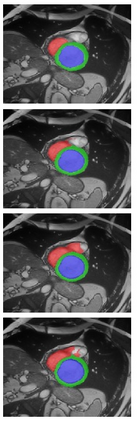

Transformer, the latest technological advance of deep learning, has gained prevalence in natural language processing or computer vision. Since medical imaging bear some resemblance to computer vision, it is natural to inquire about the status quo of Transformers in medical imaging and ask the question: can the Transformer models transform medical imaging? In this paper, we attempt to make a response to the inquiry. After a brief introduction of the fundamentals of Transformers, especially in comparison with convolutional neural networks (CNNs), and highlighting key defining properties that characterize the Transformers, we offer a comprehensive review of the state-of-the-art Transformer-based approaches for medical imaging and exhibit current research progresses made in the areas of medical image segmentation, recognition, detection, registration, reconstruction, enhancement, etc. In particular, what distinguishes our review lies in its organization based on the Transformer's key defining properties, which are mostly derived from comparing the Transformer and CNN, and its type of architecture, which specifies the manner in which the Transformer and CNN are combined, all helping the readers to best understand the rationale behind the reviewed approaches. We conclude with discussions of future perspectives.